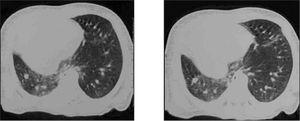

Con este cuadro clínico, ante la presencia de dificultad respiratoria inmediata y desplazamiento del latido hacia la derecha, se realiza radiografía de tórax urgente (fig. 1) apreciándose una opacificación en hemitórax derecho, sin visualizarse claramente la silueta cardíaca, no objetivándose neumotórax. El pulmón izquierdo parece mostrar una hiperinsuflación compensadora. Se realizan además: hemograma: normal. Gasometría capilar: mínima acidosis respiratoria. Hemocultivo: negativo. Ecografías abdominal y craneal: normales. Ecocardiografía: situs solitus. Dextroposición con levoápex, comunicación interauricular amplia con cortocircuito izquierda-derecha, comunicación interventricular perimembranosa de 4-5 mm tapada por tejido accesorio de la válvula tricúspide, ductus arterioso persistente con cortocircuito izquierda-derecha. Cariotipo: masculino normal (46XY).

Figura 1. Radiografía simple de tórax: opacificación de hemitórax derecho. Hiperinsuflación compensadora de pulmón izquierdo. No evidencia de aire ectópico.